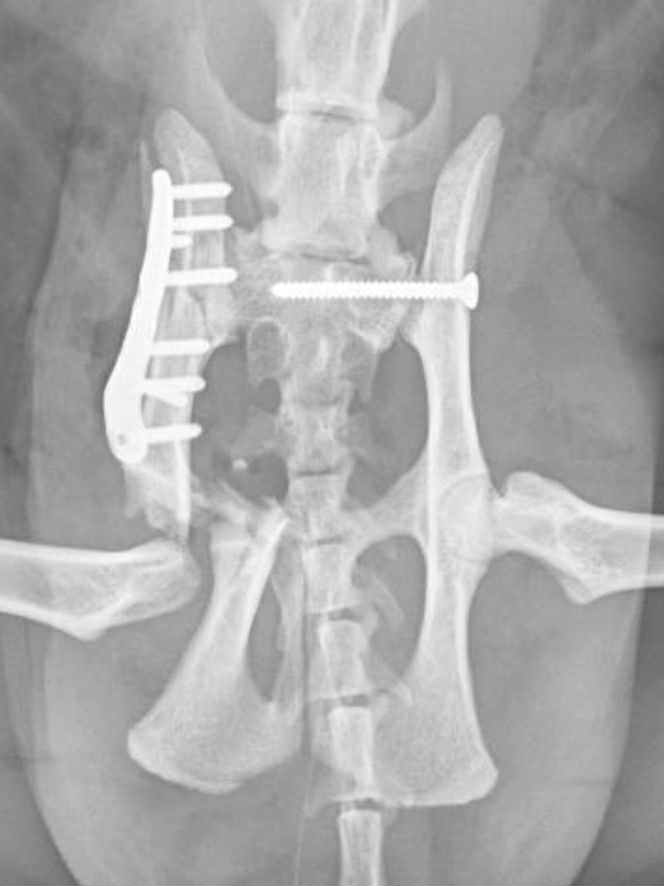

Monday was a long day. I spoke to vet who was going to operate first thing on Monday, and she explained the surgical plan for the day. She planned to put a screw in one side to pin the pelvis at that side to Ragnar’s sacrum. At the other side where the damage was worse, she proposed to plate and pin the top part of his pelvis but as the socket for his hip joint had been destroyed, she would also need to remove the head of his femur to allow the leg to sit in the correct position and give him the best chance of good use of it. The vet estimated that it would take her five hours in theatre.

My boy is a warrior. He sailed through the surgery, thanks largely to skill of the veterinary team. The vet did apologise that they had had to shave quite a lot of his fur off and that once we got over the shock of seeing him, we would find his temporary look funny.